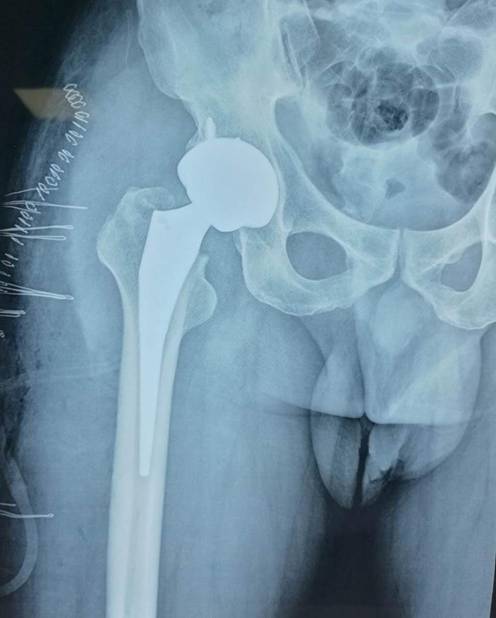

全髋关节置换术治疗股骨头坏死

优点:手术成熟,疗效确切。

术前术后对比

全髋关节翻修术